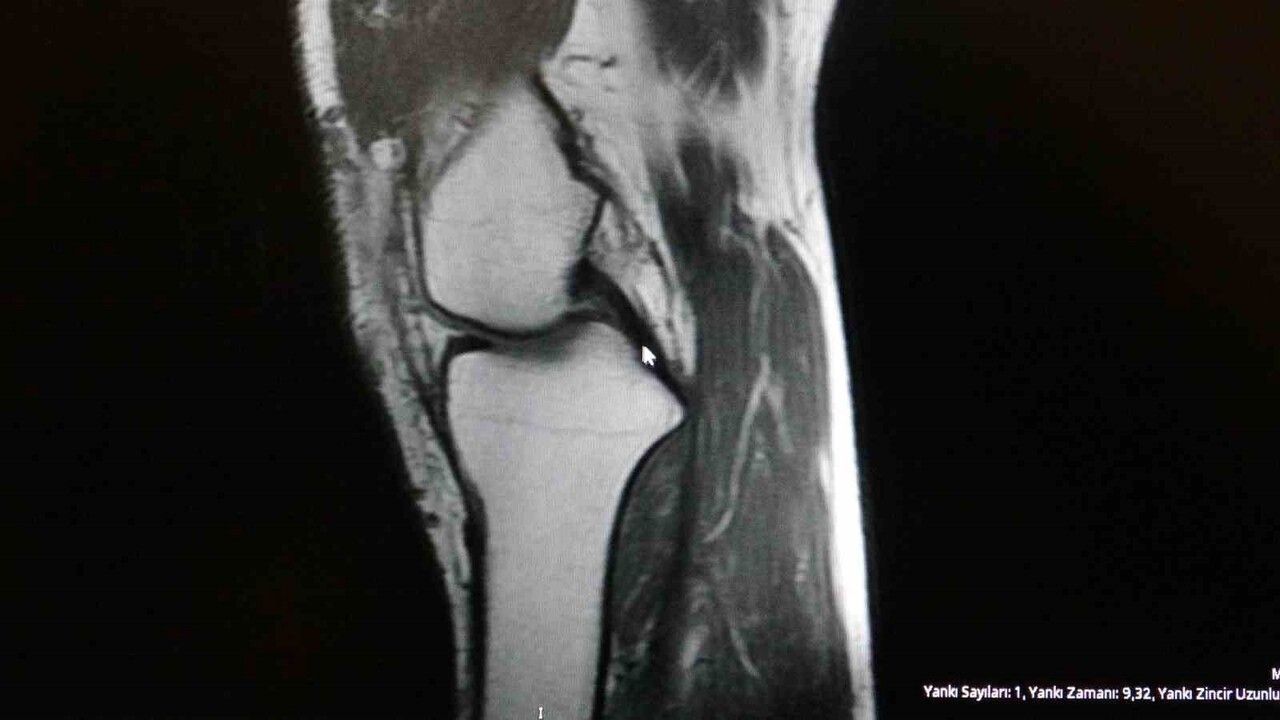

Ortopedi polikliniklerine en sık başvuran yaralanmaların ayak bileği, diz ve omuzda olduğunu belirten Demirbaş, futbolun yaralanma oranlarının en yüksek olduğu branşlardan biri olduğunu ifade etti. Bu bağlamda, menisküs yırtıkları, ön çapraz bağ yırtıkları ve aşil tendon kopmalarının sık görüldüğünü söyledi.